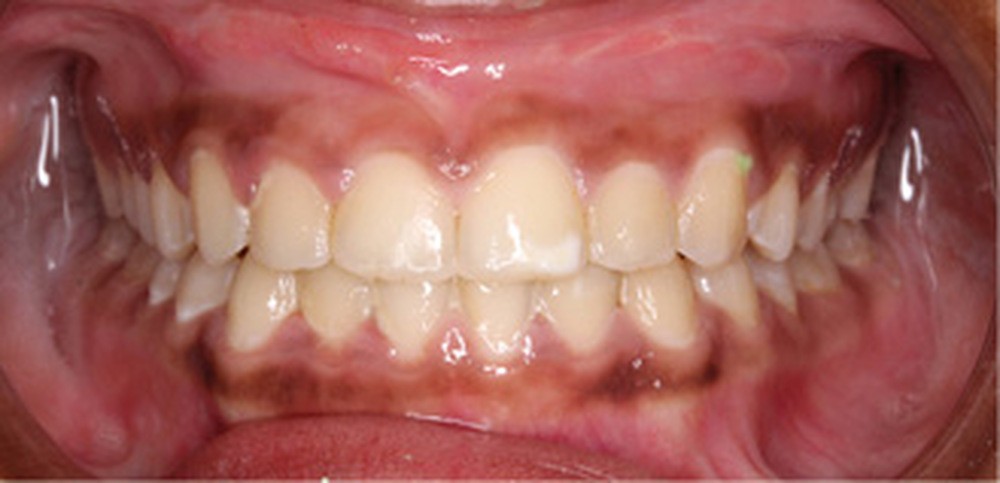

Examen clinique (fig. 1a-h)

À l’examen de face, Anisa présente un visage ovalaire, des hémifaces symétriques, des lignes horizontales parallèles, une augmentation de l’étage inférieur, une occlusion labiale légèrement forcée et des dents mandibulaires exposées au sourire. Les profils général et sous-nasal sont concaves avec un angle naso-labial augmenté et une prochéilie inférieure.

L’examen clinique endo-buccal révèle une denture adulte jeune avec un inversé d’articulé antérieur de 13 à 23, des tatouages gingivaux ethniques et des taches de décalcifications, un parodonte sain mais un brossage insuffisant.

L’arcade maxillaire est en V et la voûte palatine profonde. L’arcade mandibulaire a une forme en U (non-concordance des formes d’arcade) et présente des malpositions des dents cuspidées. La médiane mandibulaire est décalée à gauche de 2 mm ; le recouvrement antérieur est de 2 mm ; les molaires sont en classe III avec un surplomb inversé.